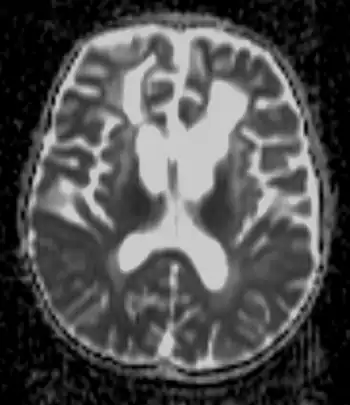

| Brain of a 4-year-old boy with Alexander disease showing macroencephaly and periventricular leukomalacia (note brownish discoloration around the cerebral ventricles) | |

Detecting the signs of Alexander disease is possible with magnetic resonance imaging (MRI), which looks for specific changes in the brain that may be tell-tale signs for the disease.[11][12] It is even possible to detect adult-onset Alexander disease with MRI.[10] Alexander disease may also be revealed by genetic testing for its known cause.[13][14] A rough diagnosis may also be made through revealing of clinical symptoms, including enlarged head size, along with radiological studies, and negative tests for other leukodystrophies.[8]

A CT scan shows:

- Decreased density of white matter

- Frontal lobe predominance

- Dilated lateral ventricles may present